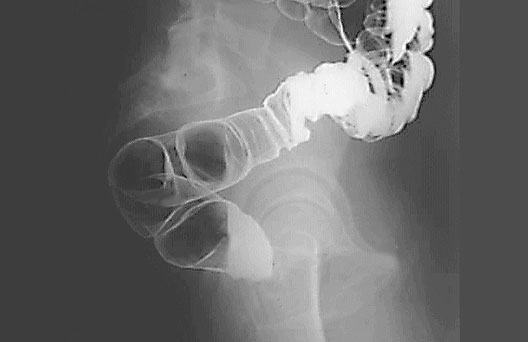

Barium Enema

1. Sacrum

2. Sigmoid Colon

3. Rectum

4. Barium in sigmoid colon

5. Pubis bone

6. Femur